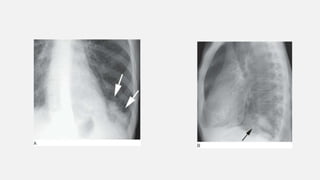

• #23 : Ill-defined fluffy consolidation (white arrows) is visible on CT in a patient with right lower lobe pneumonia. Small focal lucencies (black arrows) within the area of consolidation are “air alveolograms.”

• #24 Consolidation: patchy opacities. A: Chest radiograph in a patient with pulmonary edema due to renal failure shows patchy perihilar consolidation. B: Patchy areas of fluffy consolidation are seen on CT. The fluffy margins are due to variable involvement of alveoli at the edges of the pathologic process.